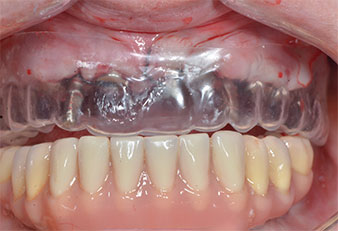

Drei Jahre später war es Zeit für eine gleichartige Oberkieferprothese. Basierend auf der DVT-Planung wurde durch Verwendung kurzer Implantate eine Sinusaugmentation vermieden und die geplanten Implantatpositionen wurden mit einer Bohrschablone auf den Kieferkamm übertragen (Abb. 1 und 2).

Abb. 1: Präoperative Ansicht des Kieferkamms, die Implantatpositionen wurden mithilfe einer Kunststoff-Bohrschablone markiert. Wegen des niedrigen Kieferkamms sind im Seitenzahnbereich sehr kurze Implantate geplant.